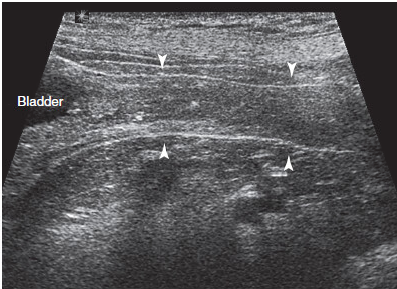

What is this?

Urethral plug/obstruction in a male cat